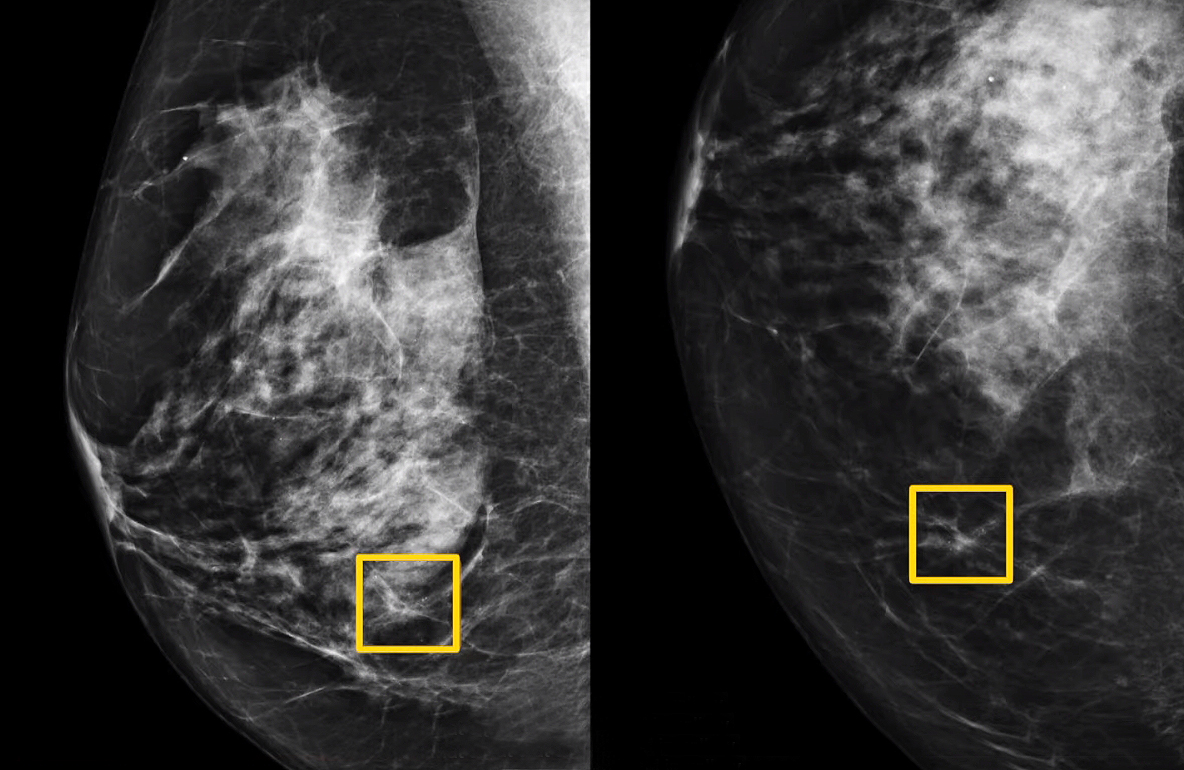

유방암은 자가진단을 통해 응어리를 발견한다든가 유방 변형 등을 확인할 수 있습니다.

유방암 자가진단 방법은 먼저 거울 앞에 서서 자신의 유방을 유심히 살펴보고 촉진을 통해 확인하는 것입니다. 특히 다음과 같은 사항들을 주의 깊게 관찰해야 합니다.

유방암 자가진단법

1. 멍울 또는 함몰

보통 만져지는 멍울이 있는 곳을 부드럽게 눌러보고 유방을 움직여 함몰된 곳이 있는지 찾아봅니다. 함몰되는 곳이 있거나 유두가 치우친 것이 확인되면 암을 의심해 볼 수 있습니다.